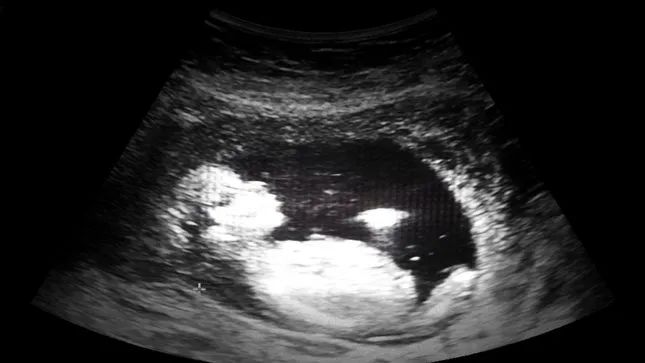

据“科学警告”网站(ScienceAlert)公布,科学家们首次在人类婴儿胎盘中发现了微型塑料颗粒。研究人员在无塑料环境中收集了6位正常妊娠的健康妈妈的胎盘,并最终利用拉曼显微光谱在四个胎盘中检测到了12块5至10微米大小的微塑料颗粒。

图源:ScienceAlert

不仅如此,研究表示,这些塑料颗粒分别位于胎盘的胎侧、母侧以及胎儿发育的羊膜中,这意味着,胎盘的所有部位都存在微塑料碎片。最恐怖的事,这只是研究人员仅对每个胎盘中约4%的部分进行了分析,这表明微塑料在胎盘中的总数会更多。

图源:TheHill

在显微镜头下,这些颗粒都是经过染色加工的蓝色、红色、橙色或粉色塑料,可能最初来自包装、涂料、化妆品和个人护理产品,被母体吸收或吸入体内。大部分颗粒大小在10微米(约0.01毫米)之内,这表明它们足够小,可以进入人体血液中。这些微塑料颗粒可能已经进入了婴儿的体内,但目前研究人员无法进行评估。

罗马圣乔瓦尼·卡利比塔医院妇产科主任、该研究负责人安东尼奥·拉古萨博士表示:“如果在胎盘中发现了什么成分,这意味着在婴儿中也会发现同样的成分……他们就像‘赛博朋克式’婴儿,不再单纯由人类细胞组成,而是生物和无机物的混合体。”

研究人员在论文中写道:“胎盘作为胎儿与外部环境的接口,潜在有害塑料颗粒的存在是一个非常令人担忧的问题。我们科学家们需要进一步研究,来评估微塑料的存在是否可能触发免疫反应或可能导致有毒污染物的释放,从而对胎儿造成伤害。”

拉古萨博士指出,微塑料对胎儿的潜在影响包括减缓胎儿生长,或影响儿童的基因表达方式,导致发育变化等等。此外,上述研究中另外两名女性的胎盘中并没有发现这种微塑料颗粒,研究人员表示,这可能是由于生理、饮食或生活方式不同造成。